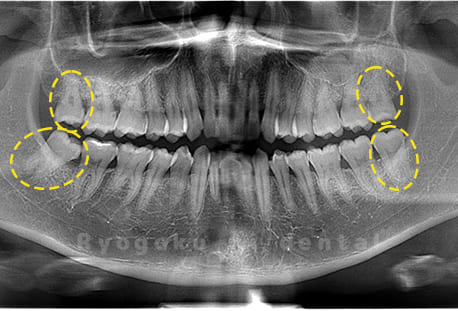

水平埋伏の親知らず

歯茎の中で完全に横に生えてしまうタイプです。

この親知らずを水平埋伏智歯と言います。このタイプはほとんどが下顎のケースです。真横に生えているので抜歯の際は難易度が高く2~3つに砕いて分けて抜歯をします。